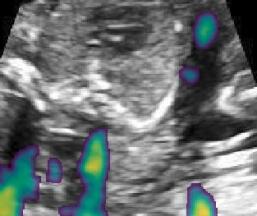

Fig. 6 compares the shadow confidence maps of the state-of-the-art methods and the proposed methods. RW and have the same parameters as used for Table I. The shadow confidence maps of the baseline, the proposed method and the proposedAG method are generated directly from input shadow images by confidence estimation networks. Overall, the proposed method and the proposedAG method achieve more visually reasonable shadow confidence estimation than the baseline and the state-of-the-art on different anatomical structures shown in Fig. 6. The proposed method and the proposedAG method are able to highlight multiple shadow regions while the RW algorithm shows limitations for most cases, especially for disjoint shadow regions.

Row I in Fig. 6 shows a fetal brain image from . The confidence estimation of shadow regions from the baseline, the proposed method and the proposedAG method are similarly accurate since we use fetal brain images to train the confidence estimation networks in these three methods. These outperform [16] and [22]. Rows (II-IV) in Fig. 6 show shadow confidence maps of non-brain anatomy from , including lips, abdominal and cardiac. The baseline failed on unseen data during inference. However, the proposed methods are able to generate accurate shadow confidence maps because of the generalized shadow features obtained by the shadow-seg module. Furthermore, the “Lips” example shows that our method is capable of detecting weaker shadow regions that have not been annotated in manual segmentation. This indicates that the confidence estimation network has learned general properties of shadow regions.